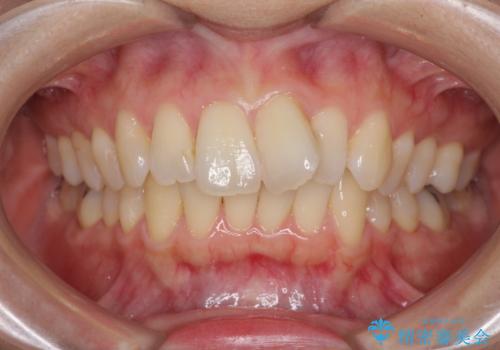

全体のガタガタをインビザラインできれいな歯並びへ